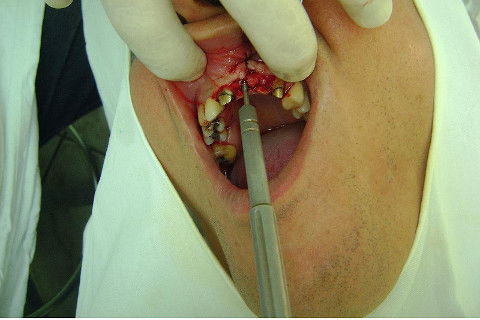

Cirurgia realizada hoje de manhã...No planejamento percebi medindo espessura do rebordo com especímetro que as medidas não estavam muito boas, ou o ideal, em torno de 4,5 a 5 mm ate´o terço médio do rebordo e melhorava no final, com 6 a 7 mm. Optei então por uma pequena expansão usando os expansores rosqueáveis. Aconteceu uma pequena fenestração na hora da fixação dos implantes, especialmente na região do 22 que fraturou o início da tábua óssea, mas não me preocupei porque não foi mais do que 2 mm de fratura em direção apical, o implante ficou infraósseo e com boa estabilidade (60 N no 21 e 40 N no 22). Esta fratura tb não deixou osso completamente solto, foi do tipo galho verde, deixei em posição e suturei normalmente. Só não fiz e nem estava planejado carga imediata mesmo, mais pelo motivo da oclusão inadequada do caso.

Fotos do caso